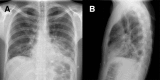

Simultaneous bilateral pneumothorax in an immunocompromised HIV patient with Pneumocystis jirovecii pneumonia

Pneumocystis in humans is caused by a unicellular and eukaryotic organism called P. jirovecii. The overall incidence of P. jirovecii pneumonia (PCP) has decreased with the use of highly active antiretroviral therapy and the use of chemoprophylaxis with trimethroprim sulfametoxazole (TMP/SMX) in cases of immunosuppressed patients. However, approximately 85% of patients with advanced HIV infections continue to experience this disease with inadequate management. Pneumocystis infection can present with spontaneous pneumothorax in 2-6% of cases [8] which can be a potentially fatal complication. We report the case of a 32-year-old man presented with P. jirovecii pneumonia who developed cystic lesions and spontaneous bilateral pneumothorax in spite of TMP/SMX treatment. We consider it an interesting clinical case because few simultaneous bilateral pneumothorax cases have been described directly related to the PCP.